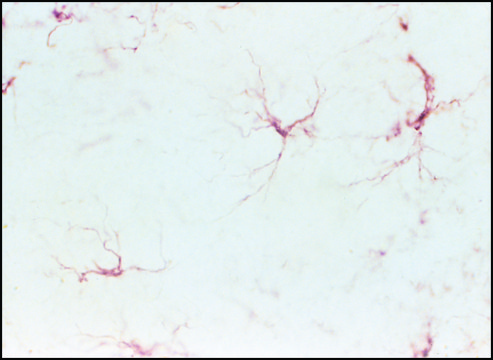

Contain universal reagents for use with primary antibodies in immunohistology, ELISA, and immunoblotting.

ExtrAvidin® is a unique form of avidin, available only from Sigma, that combines the high specificity and affinity of avidin for biotin with low non-specific binding at physiological pH. ExtrAvidin® peroxidase exhibits high sensitivity with low background.

Immunohistochemistry (1 paper)